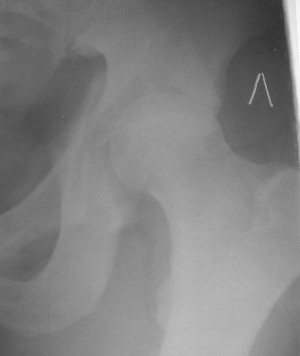

Контрольный снимок перед разрешением нагрузки прямой 13/10/03

Перед разрешением нагрузки боковой 13/10/03

Два месяца нагрузки без костылей 19/12/03

Еще месяц 20/02/04

Больной 18 мая 2003 года в автоаварии получил перелом левой вертлужной впадины, вывих бедра. Госпитализирован в один из стационаров области.Вывих вправлен. В последствии бедро вывихивалось еще дважды. На консультацию был представлен снимок от 19.05.03г., больной переведен к нам 3.06.03г. Снимок при поступлении - перелом впадины, задне-верхний вывих бедра. 05.06.2003 г. выполнено открытое вправление вывиха левого бедра и остеосинтез стенки вертлужной впадины двумя винтами. Послеоперационный период без осложнений. Объем движений в левом тазобедренном суставе восстановился полностью. Выписан на амбулаторное лечение в удовлетворительном состоянии с рекомендациями 3 месяца ходить на костылях без нагрузки на оперированную конечность. На контрольных рентгенограммах левого тазобедренного сустава 13.10.2003 г. - признаки консолидации перелома; плотность, форма головки и состояние суставных поверхностей удовлетворительные. Разрешена дозированная осевая нагрузка, на конечность с использованием дополнительной опоры. 19.12.2003 г. больной обратился с жалобами на боли в левом тазобедренном суставе. На рентгенограммах левого тазобедренного сустава 19.12.2003 г., 20.02.04г. - асептичекий некроз головки бедра. 5.04.04г. - эндопротез. Сейчас ходит без трости, не хромает. Особенность эндопротезирования - при удалении винтов прослежена линия перелома заднего края впадины и предложено установить чашку несколько меньшего диаметра, чтобы она была покрыта несломанной частью.